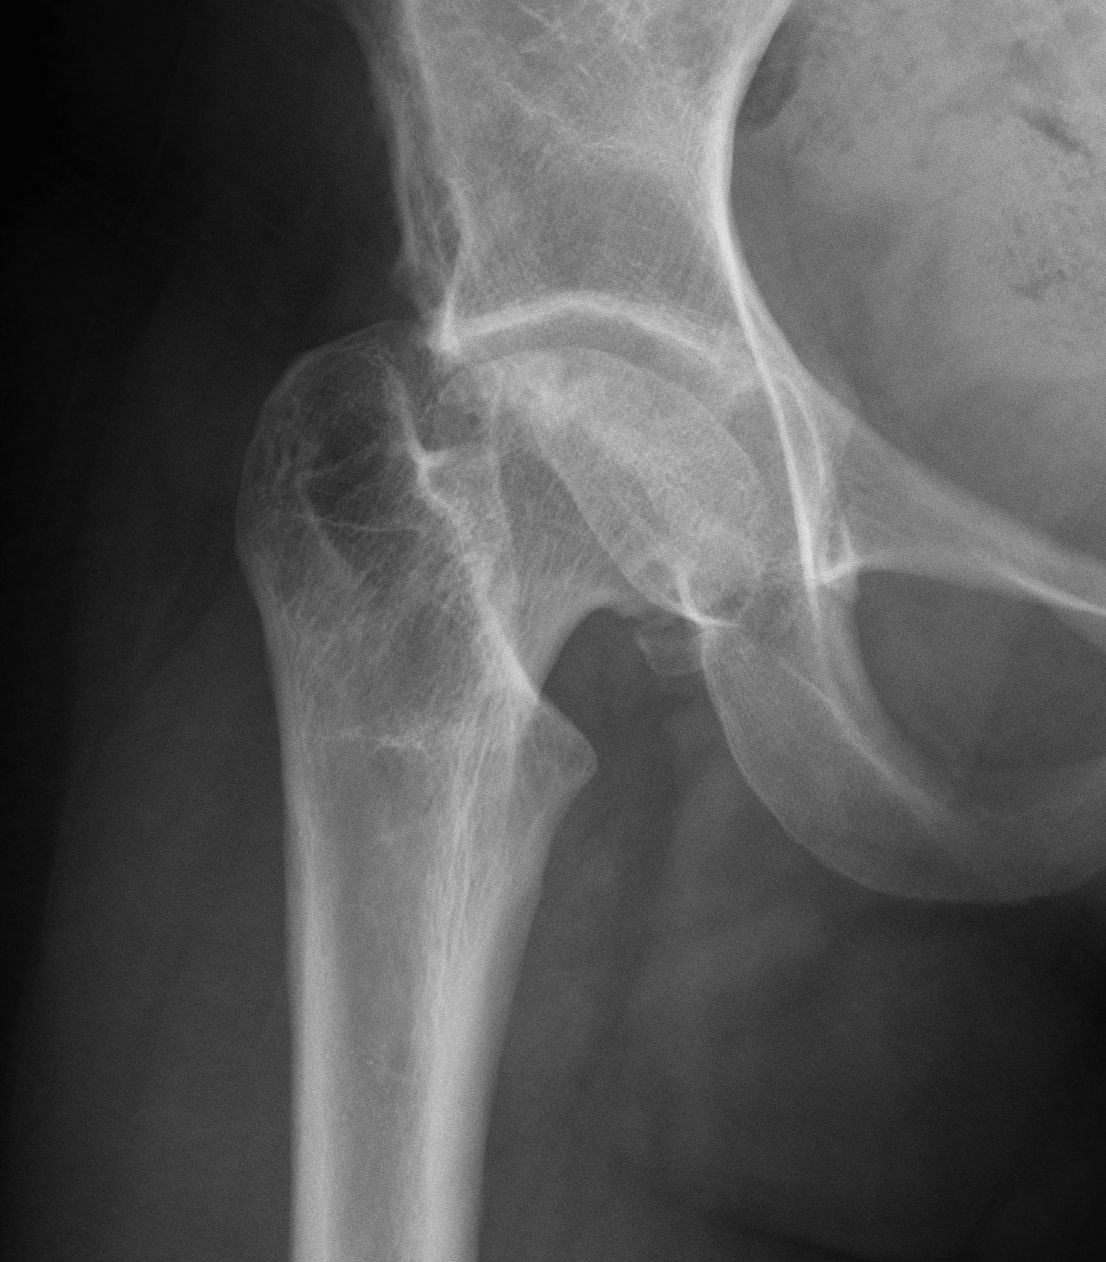

| Femur | Acetabulum | Leg Length Discrepancy | Abductors |

|---|---|---|---|

|

Multiplanar deformity |

Element dysplasia | 2 - 4 cm | Shortened |

| Worsened by previous surgery | May need trochanteric slide | ||

| Risk of intra-operative fracture | |||

| May require osteotomy |

Shallow acetabulum